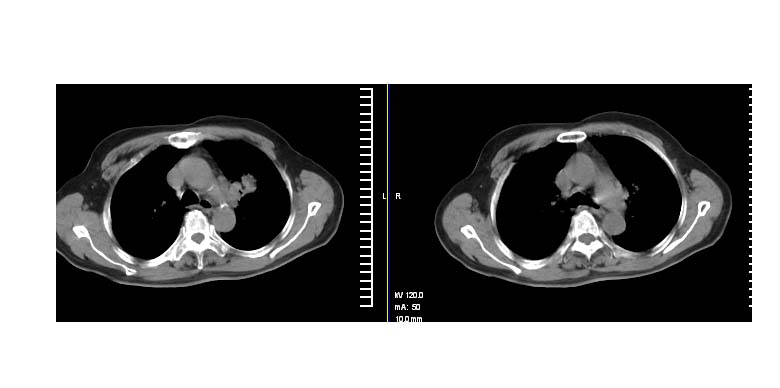

标题: CT11087:男性,82.咳嗽一周.抗炎治疗4-5天效果不明 [打印本页]

标题: CT11087:男性,82.咳嗽一周.抗炎治疗4-5天效果不明

考虑左上肺癌,似与左侧肋骨关系密切?

左上肺周围型肺癌伴纵隔淋巴结转移

左上肺实质性肿块,浅分叶 毛糙 胸膜凹陷征 纵隔淋巴结肿大——支持:左肺上叶周围型肺癌!

左上肺软组织肿块,有分叶,短毛刺,气管旁间隙见有肿大淋巴结,考虑左上周围型肺癌伴纵隔淋巴结转移。